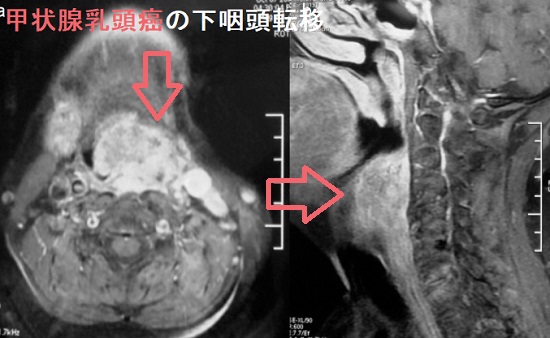

若年性血管線維腫は放射線治療が行われ放射線誘発性甲状腺がんの問題があった。喉頭乳頭腫はヒトパピローマウイルス(HPV)感染が原因の良性腫瘍だが稀に癌化。甲状腺乳頭癌の副咽頭間隙転移、下咽頭転移はまれ。喉頭癌・下咽頭癌(扁平上皮癌)の甲状腺転移がある。上咽頭扁平上皮がんはヘルペスウイルスの一種、EBウイルス(エプスタイン・バールウイルス)が主な原因。未分化扁平上皮がんが多く、放射線感受性が高いため放射線根治治療になり、放射線甲状腺炎や放射線唾液腺炎の合併症・後遺症が生じる。